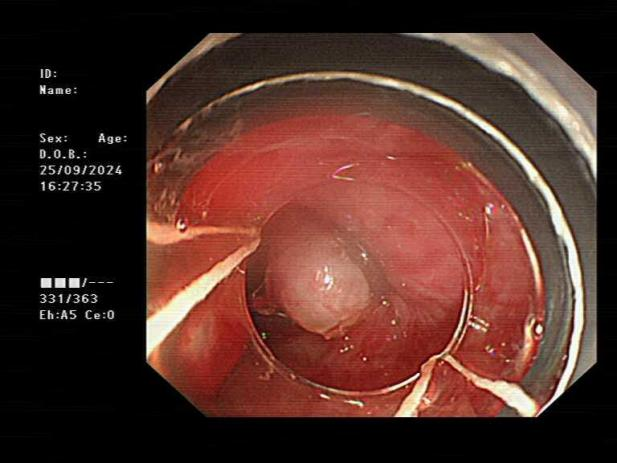

消化内科团队与患者及家属充分沟通病情后,面对高风险的情况,秉持“救死扶伤”的宗旨,顶着压力冷静沉着为患者行急诊胃镜检查。胃镜显示食管中下段可见四条静脉曲张,最大直径约1.0cm,交通支形成,红色征阳性,食管中段距门齿30cm及下段距门齿38cm各见一处白色血栓头;下段距门齿32cm偏后壁静脉曲张可见一破裂口并活动性喷射样出血。经患者家属签字同意,消化内科团队凭借熟练、过硬的内镜技术,顺利完成“经内镜食管静脉曲张破裂出血硬化止血术+经内镜食管静脉曲张套扎止血术”。

食管静脉曲张白色血栓头

食管静脉曲张喷射样出血